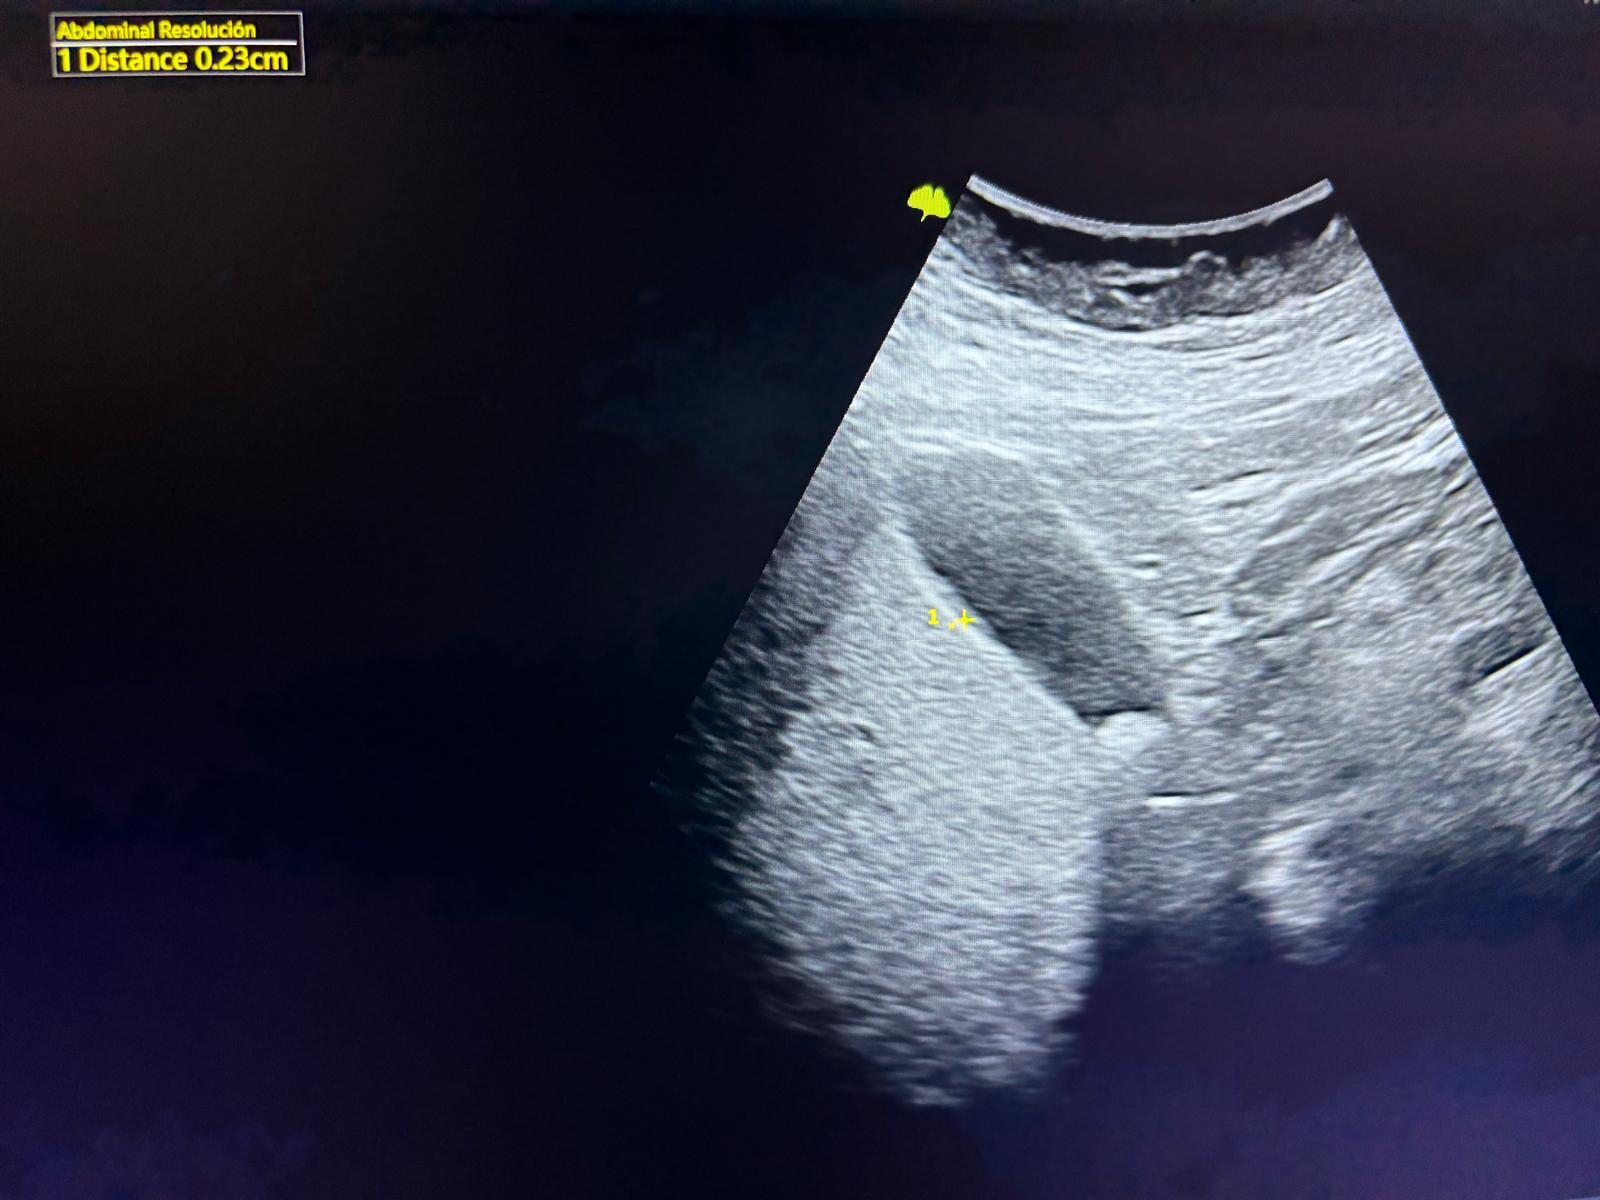

Hallazgos ecográficos

Vesícula biliar de 5,89 x 2,74 cm no distendida, paredes finas de 0,23 cm. Se visualiza imagen hiperecogénica redondeada única de 1 x 0,67 cm en infundíbulo con sombra posterior sugestiva de litiasis.